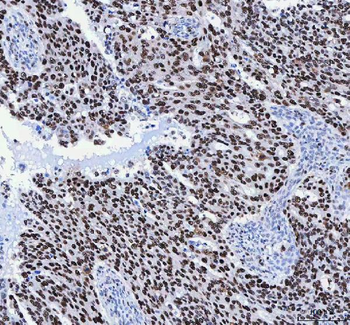

![Anti-FEN1 [SAIC-21C-4]](/images//pub/media/catalog/product/NewWebsite/35/orb1089994_1.png)

![Anti-FEN1 [SAIC-21C-4]](/images/pub/media/catalog/product/NewWebsite/35/orb1089994_2.png)

![Anti-FEN1 [SAIC-21C-4]](/images/pub/media/catalog/product/NewWebsite/35/orb1089994_3.png)